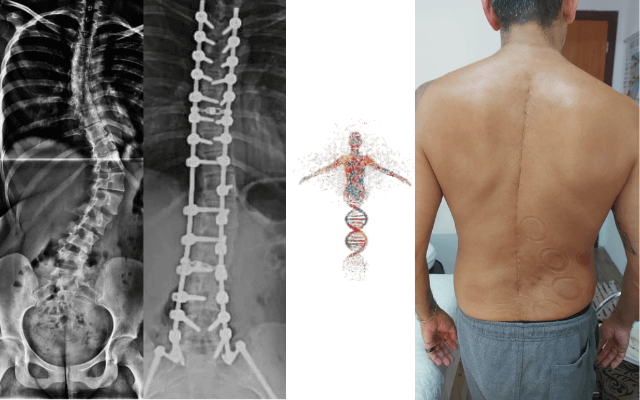

Veja alguns resultados de pacientes